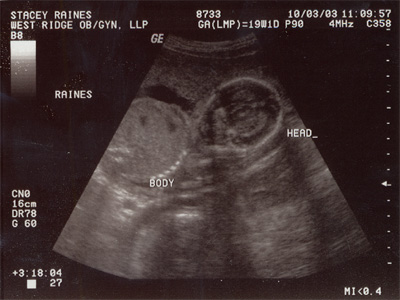

| Here

is one of the first photos of our brother or sister. What

do you think, can you tell us anything from the picture? |

| This

picture is all Ashlyn and I have to go on.